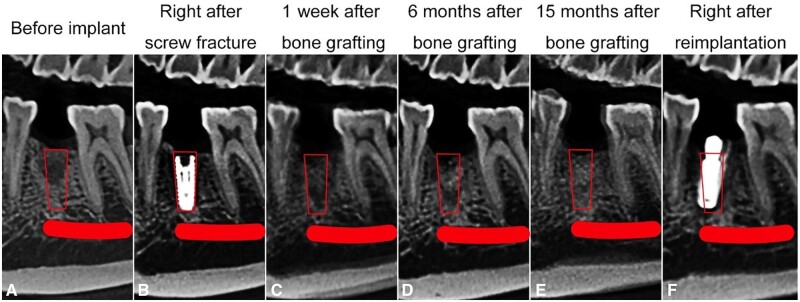

Sagittal CBCT sections at different time points: (A) before implant, (B) immediately after screw fracture, (C) 1 week after bone grafting, (D) 6 months after bone grafting, (E) 15 months after bone grafting and (F) immediately after reimplantation. The red box represents the bone defect, and the red line indicates the mandibular nerve canal.

CBCT was performed at 1 week, 6 months and 15 months postoperatively to assess bone regeneration. Anatomical markers were used for standardization during image reconstruction. The images were compared with those obtained before implantation (Figures 1–3). The bone defect was marked as a red box or oval, and the mandibular neural canal was marked as a red line or dot.

The horizontal plane passed through the top of the fractured screw, approximately 23 mm above the lower border of the mandible (Figure 1). The pulp cavity of tooth #27 and the distal buccal pulp cavity of tooth #30 were marked as points 1 and 2, respectively, in this section. The sagittal plane was based on these two points, perpendicular to the horizontal plane (Figure 2). The coronal plane was defined as a plane at the midpoint between points 1 and 2, perpendicular to the sagittal plane (Figure 3).

The boundary of the bone defect was not obvious because the densities of SD-FDBA and native bone were similar. However, the defect could be visualized, particularly in the apical half (Figures 1C and 2C). The density of the bone defect increased with time, and the defect boundary remained unclear at 6 and 15 months (Figures 1–3). It indicated the trabecular hyperplasia and activity of osteoblasts and osteoclasts.

To quantitatively compare the dimensional changes due to implant extraction and grafts implantation, the height and width of the alveolar ridge were measured 1 week, 6 months and 15 months after bone grafting (Figures 1 and 3, Table 1). The percentage of remaining alveolar height or width was calculated as follows [11, 12]:

The post-extraction alveolar height was about 91% of the original value. The width increased slightly because of the overfilling of bone graft, but gradually decreased to a steady level of about 91%.